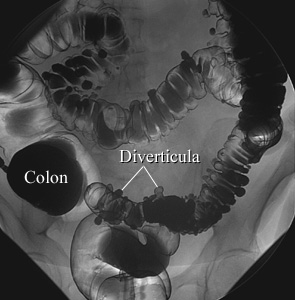

Air-Contrast Barium EnemaCourtesy of Intermountain Medical Imaging, Boise,

Idaho. All rights reserved. In an air-contrast study, the colon is first filled with barium and

then the barium is drained, leaving only a thin layer of barium on the wall of

the colon. The colon is then filled with air. This barium enema image shows

pouches (called diverticula) in the wall of the colon. ByHealthwise Staff Primary Medical ReviewerE. Gregory Thompson, MD - Internal Medicine Adam Husney, MD - Family Medicine Martin J. Gabica, MD - Family Medicine Specialist Medical ReviewerJerome B. Simon, MD, FRCPC, FACP - Gastroenterology Current as ofOctober 14, 2016 Current as of: